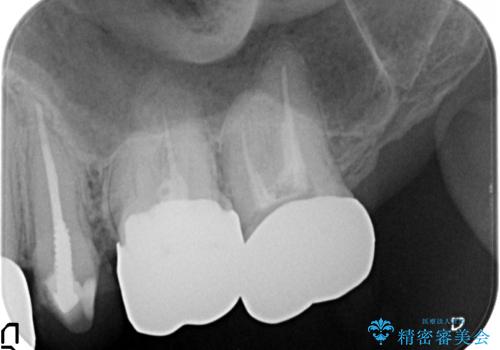

ここの歯の状態を精密に検査し、根管治療、セラミック治療、インプラント治療を含む総合的な歯科治療を計画します。